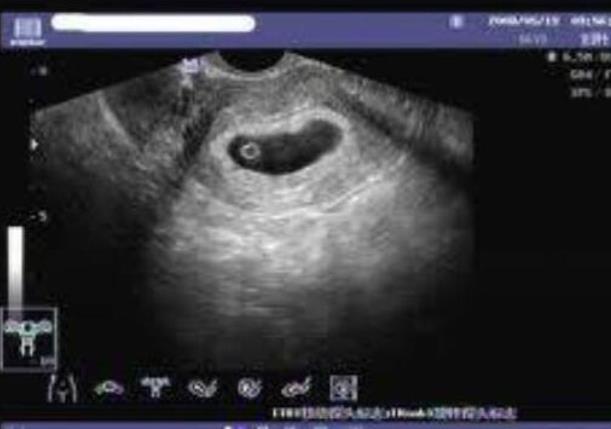

云南省試管嬰兒醫院選擇較多,但無論是在云南九州醫院還是云南省第一人民醫院做試管,成功率都因人而異,大約在40%-50%左右。然而,在云南私立機構做試管時,必須查清楚醫院的資質。近年來,許多正規生殖中心的輔助生殖周期數量逐年增加,保持了較高的成功率。以下依據15顆基礎卵泡數量預測到云南私立醫院做試管成功率,可參考下表:

云南省第一人民醫院三代成功率 云南做供卵試管最受歡迎醫院排名 ‘b超寫的哪句有可能是男孩’